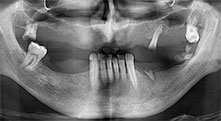

Проф. д-р Емануел Брату, лицево-челюстен хирург, орален хирург и протезист, е ръководител на имплантологичните департаменти в два румънски университета. Той управлява известна частна болница в Тимишоара и е международно признат изследовател. В това интервю Брату обяснява защо той смята, че апаратът за пиезо хирургия Piezomed на W&H и двата патентовани триони са от съществено значение за костната хирургия.

Брату: Ние използваме инструментите за събиране на костни блокове и разделяне на алвеоларни гребени. Ние също използваме Piezomed B6/B7 за остеотомия на наранени зъби и отстраняване на неуспешни импланти. Всички индикации, които изискват дълбоки, чисти разрези.

Брату: Ние предпочитаме да събираме кост от външната страна на гребена в задната част на долната челюст. След разрязване на меките тъкани, ние използваме новите триони, за да определим количеството кост, което ще събираме. С този подход, ние използваме трионите за цялата препарация в почти 80% от случаите. Може да използваме и други пиезо инструменти и накрая длето за мобилизиране на блока. Ние смятаме, че това е изключително ефективна хирургична техника.